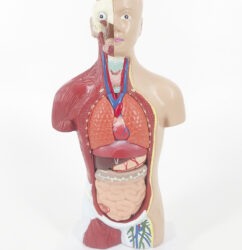

ATL-12 MALE MUSCLES FIGURE 2 PARTS

The model is an anatomically accurate representation of the human anatomy, complete with superficial and deep musculature, the digestive system, lymphatic system, respiratory system, urinary system, circulatory system, endocrine system, and nervous system. Our model has removable organs and dissectible features for a complete educational experience.

Classification:

Skeleton Models(human bone, muscle, etc.)